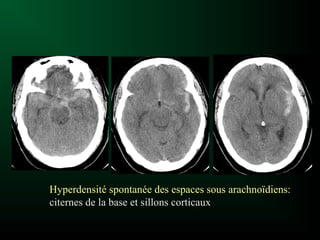

Hémorragie Sous-Arachnoïdienne

(Hémorragie méningée)

Irruption de sang ESA

Céphalée soudaine, intense

«Coup de tonnerre dans un ciel serein»

Syndrome méningé sans fièvre

La cause la plus fréquente est la rupture

d’un anévrisme intracrânien

Hémorragie méningée:

SCANNER en URGENCE !

Scanner sans injection = Examen de 1ère intention

Hyperdensité spontanée des espaces sous arachnoïdiens

HSA et Scanner

Visibilité diminue au fil des jours…

Persistance de l’hyperdensité fonction de

l’abondance du saignement

HSA et scanner normal:

– 10% des cas

– Saignement minime

– Réalisation tardive

Diagnostic = Ponction lombaire

Hémorragie sous-arachnoïdienne (HSA)

= hémorragie méningée (HM)

– post-traumatique

– rupture d’anévrisme, de MAV

– hématome intra-cérébral

souvent associé

Hyperdensité spontanée des espaces sous arachnoïdiens:

citernes de la base et sillons corticaux